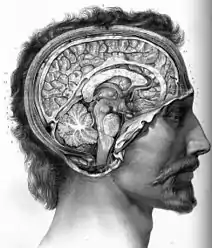

У більшості тварин, за винятком тих, у яких наявна дифузна нервова система, анатомічно виділяють центральну та периферичну частини, або центральну (ЦНС) та периферичну (ПНС) нервові системи. Якщо взяти хребетних, то у них центральна нервова система, складається з головного мозку та спинного мозку.[29] Головний мозок у свою чергу ділиться на ряд менших частин, які мають специфічну будову та забезпечують специфічні функції: довгастий мозочок, міст (тільки у ссавців і, можливо, у птахів), мозочок, середній мозок, проміжний мозок та кінцевий мозок.[32] Від головного мозку відходять черепні нерви, а від спинного – спинномозкові нерви. Ці дві групи нервів разом з нервовими вузлами та нервовими сплетеннями утворюють периферичну нервову систему.[29][33]